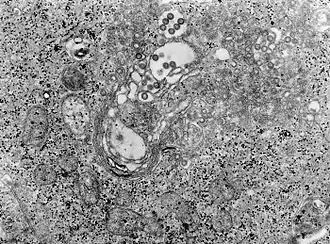

Rozpoznanie u zwierząt może być oparte na badaniu histopatologicznym wycinka pobranego z wątroby, w której w przypadku choroby dochodzi do patognomonicznych zmian – obecności martwicy i kwasochłonnych wtrętów wewnątrzjądrowych.